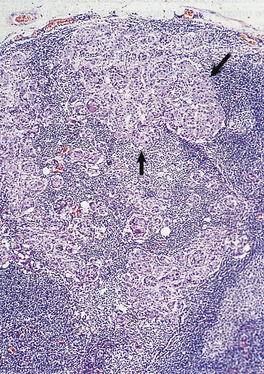

Histological grade (degree of differentiation)

The extent to which the tumour resembles histologically its cell or tissue of origin determines the tumour grade (Fig. 11.11) or degree of differentiation. Benign tumours are not usually further classified in this way because they nearly always closely resemble their parent tissue and grading the degree of differentiation offers no further clinical benefit in terms of choosing the most appropriate treatment. However, the degree of differentiation of malignant tumours is clinically useful both because it correlates strongly with patient survival (prognosis), and because it often indicates the most appropriate treatment. Thus, malignant tumours are usually graded either as well, moderately or poorly differentiated, or numerically, often by strict criteria, as grade 1, grade 2 or grade 3.

image

Fig. 11.11 Histological grading of differentiation. image Well-differentiated adenocarcinoma of the colon characterised by glandular structures similar to those in normal mucosa. image Poorly differentiated adenocarcinoma of the colon characterised by a more solid growth pattern with little evidence of gland formation.

A well-differentiated tumour more closely resembles the parent tissue than does a poorly differentiated tumour, while moderately differentiated tumours are intermediate between these two extremes. Poorly differentiated tumours are more aggressive than well-differentiated tumours.